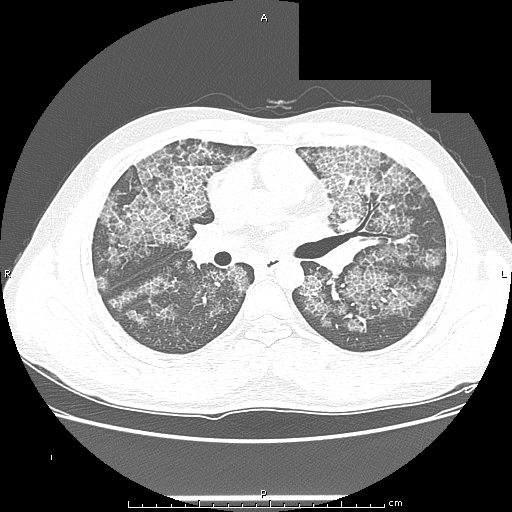

HRCT :

Ground-glass opacification, predominantly in a homogeneous distribution.

Thickened intralobular structures and interlobular septa in typical polygonal shapes, referred to as "crazy-paving“